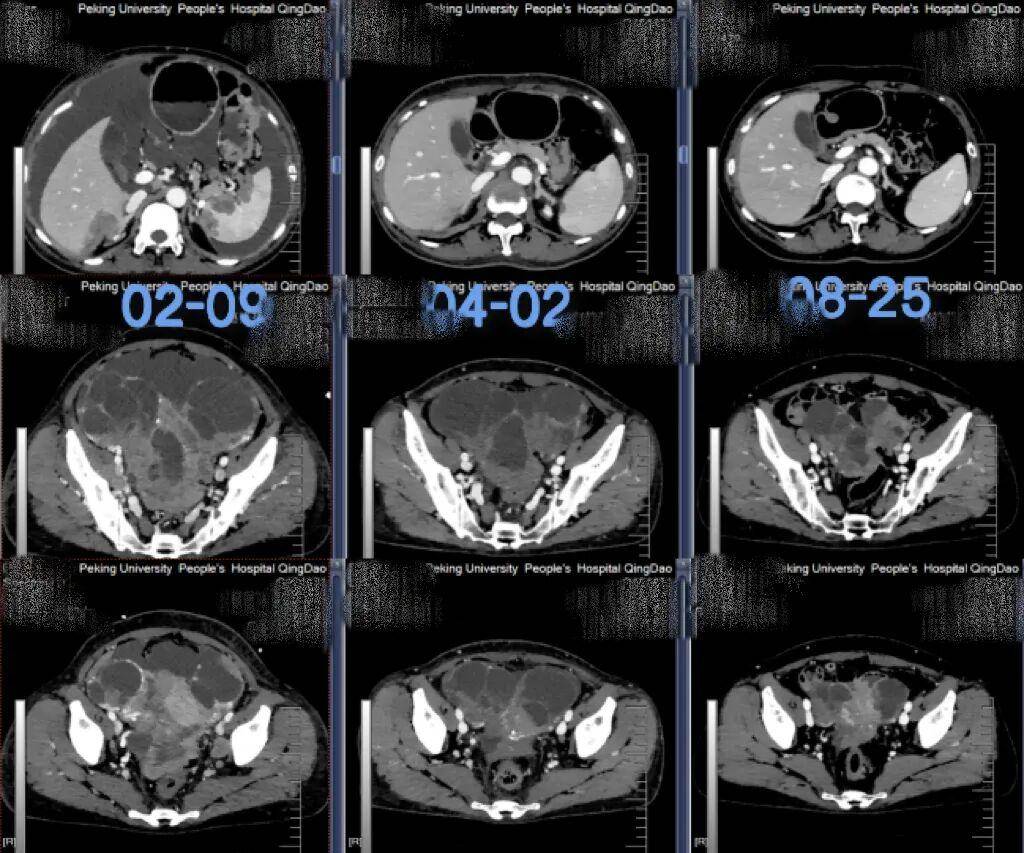

在接下来的几个月里,患者完成了数个周期的化疗。复查CT显示,肝脏、脾脏的转移灶显著缩小,胸腹水得到控制,肿瘤标志物一路下降。化疗期间,治疗团队还为她进行了腹腔灌注化疗,中医辅助治疗也全程融入,帮助她缓解不适,稳定身体状态。